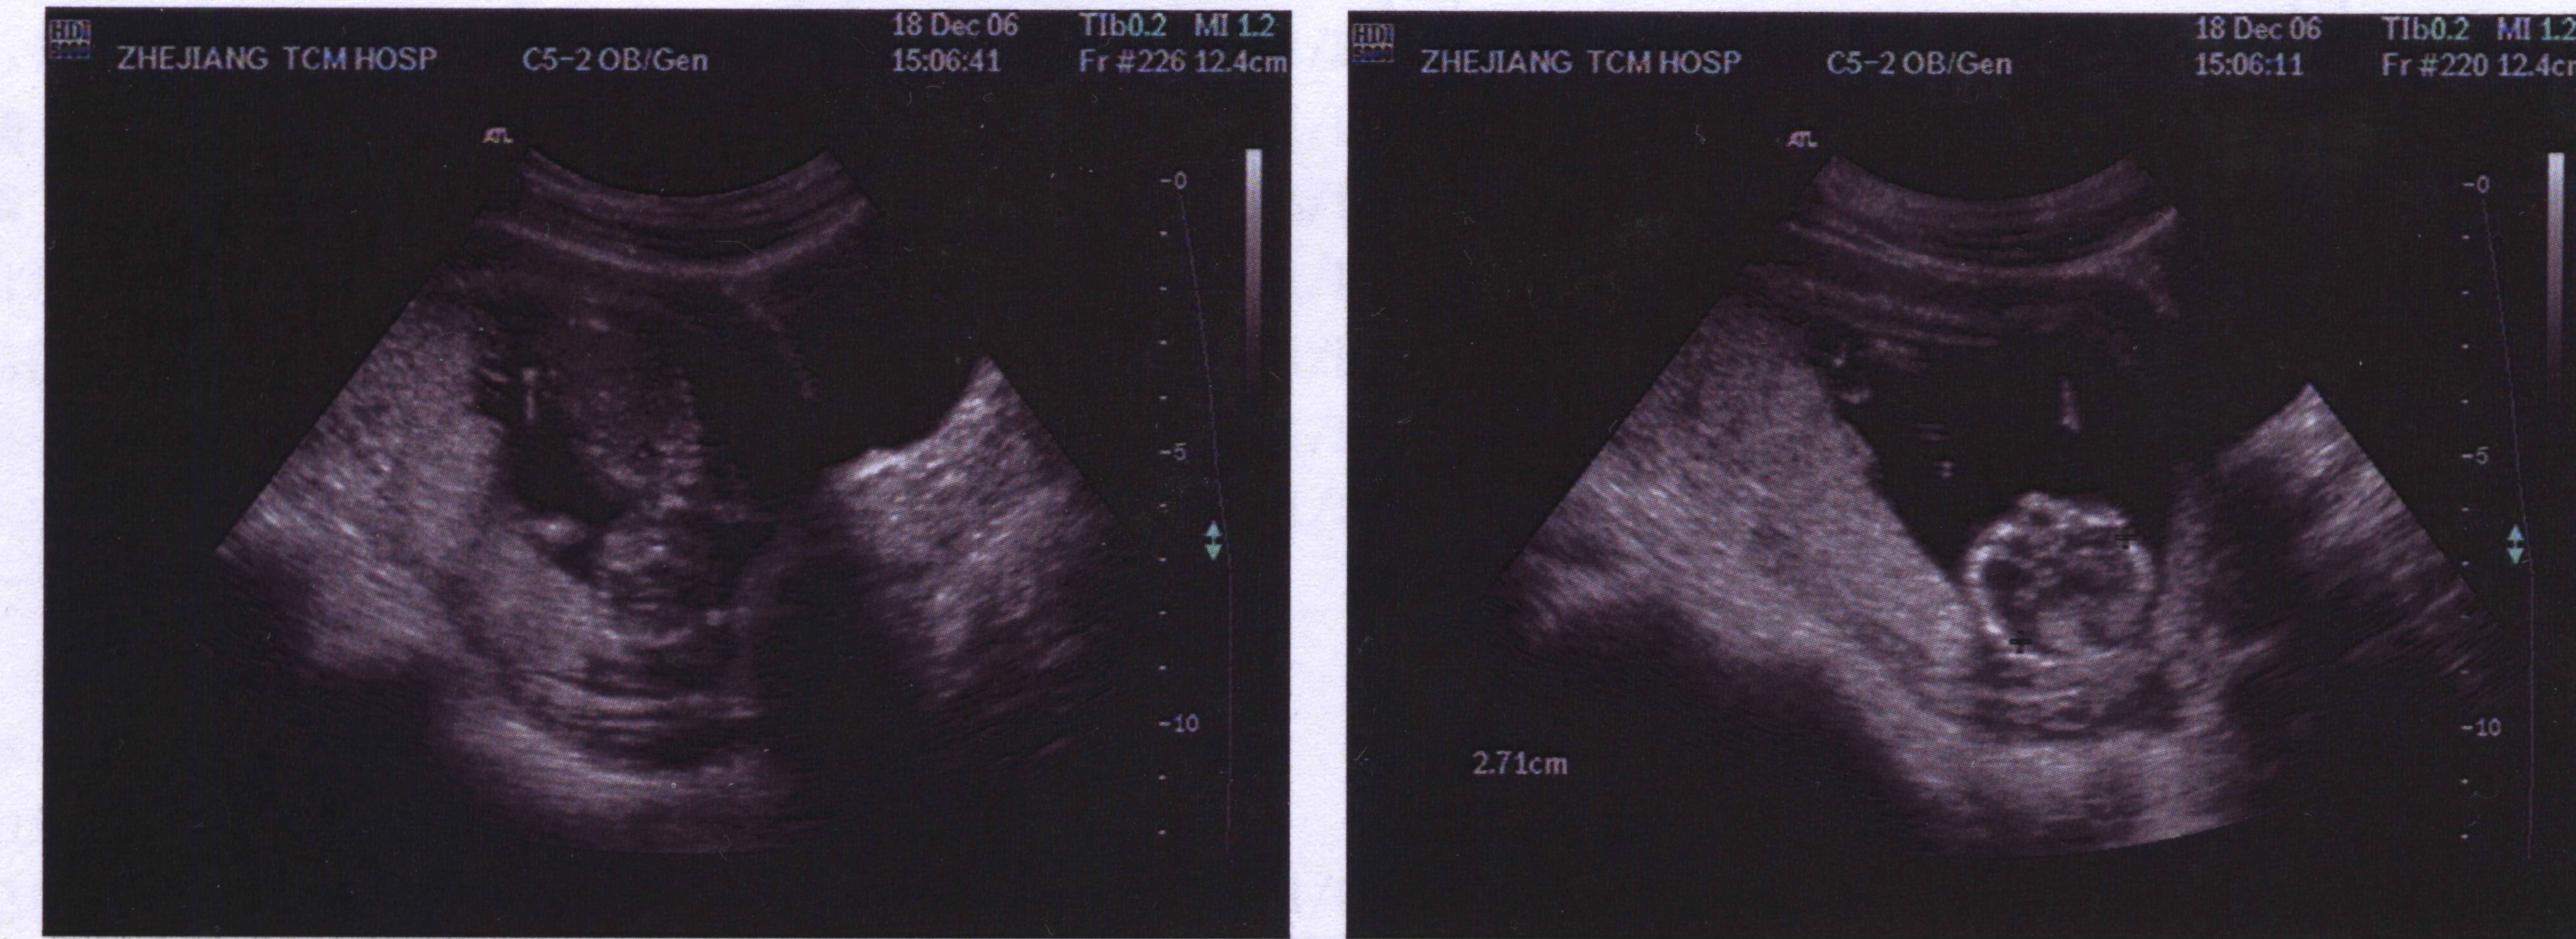

This is the first picture of the baby's mouth and hand. I watched as the picture was taken, the baby raised his hand as if to scratch his face, maybe he noticed we were watching, as he then opened his hand as if to say hello, what a wonderful feeling that was.

As you may have noticed i keep saying he, this is because i now know my feelings were right. the baby is a BOY!!!, he will be called Niall...